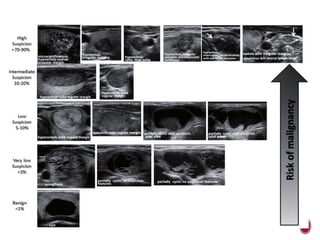

 TI-RADS classification of thyroid nodules .

• #77 1-normal,2-benign,3-probalby benign nodules,4 suscipcious.a,5-probaly malignant nodules,6-biopsy proven malignancy.